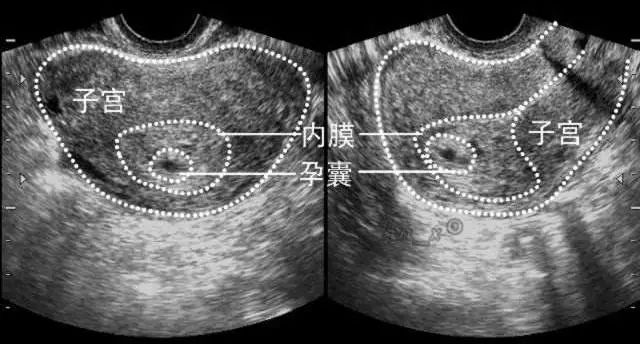

1.GS-胚囊

也称孕囊,月经规则的妇女,停经35天左右就可以观察到胚囊。随着停经时间的增加,胚囊的形状和尺寸也会变化。停经38 天左右,胚囊内可见到叫做「卵黄囊」的结构,这时我们就可以确定这是胚囊。怀孕6周左右胎囊直径约2厘米,孕10周时可达到约5厘米。